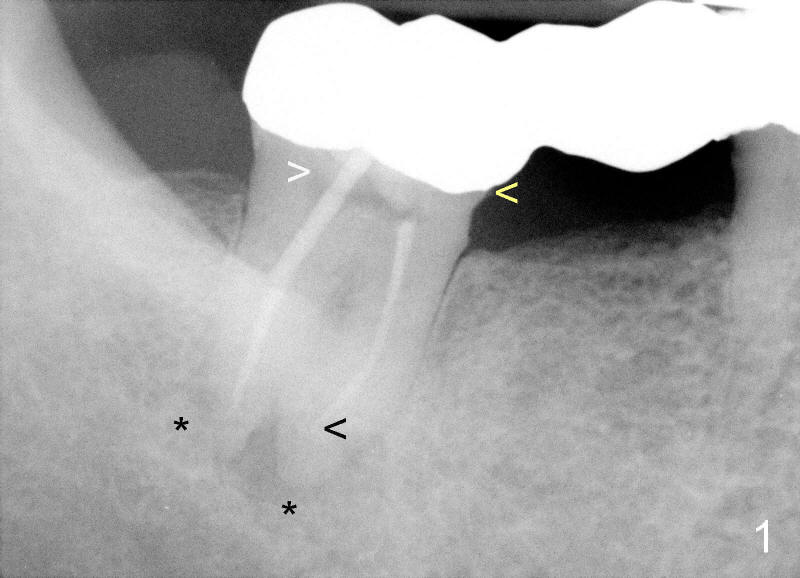

Magnification of Fig. 1 shows that #32 abutment tooth has periapical radiolucency (*) associated with both the mesial and distal roots. The root canal fillings are short (black <). The pulpal chamber is not filled (white >). In addition, the mesial margin is open (yellow <) . Return to main text